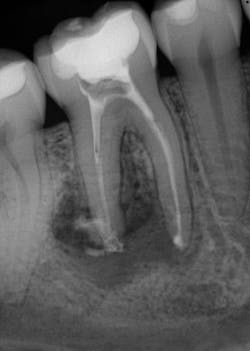

Various clinical presentations and risk factors can influence endodontic success or failure, including but not limited to the quality of the root canal performed and the seal of the coronal restoration.2 In addition to the aforementioned factors, the presence and size of a periapical lesion can directly affect the prognosis and treatment outcome. Classic literature highlights this shift in long-term success rates from 96% for vital/nonvital cases without the presence of a periapical lesion to 86% when a periapical lesion is present.3

Periapical radiographs have been commonly used to evaluate the size of periapical lesions. However, periapical radiographs have limitations, because the information is rendered in only two dimensions. A periapical lesion can only be detected in the radiograph when the mineral loss of bone reaches 30%–50%.4